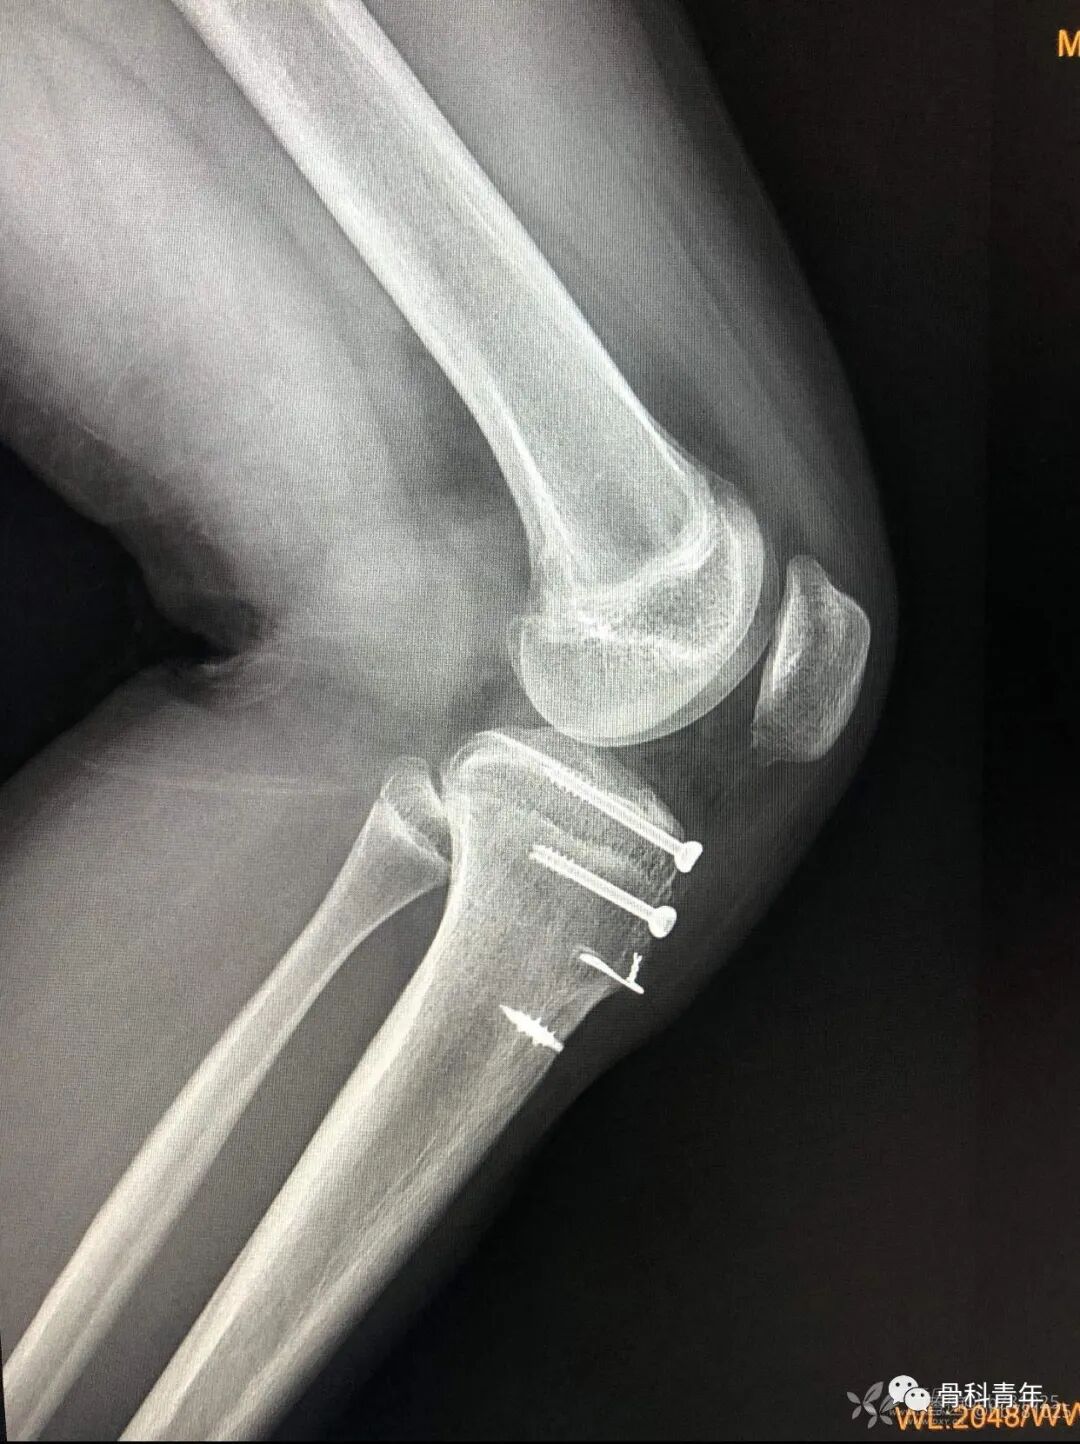

6.胫骨平台骨折(过伸伤)